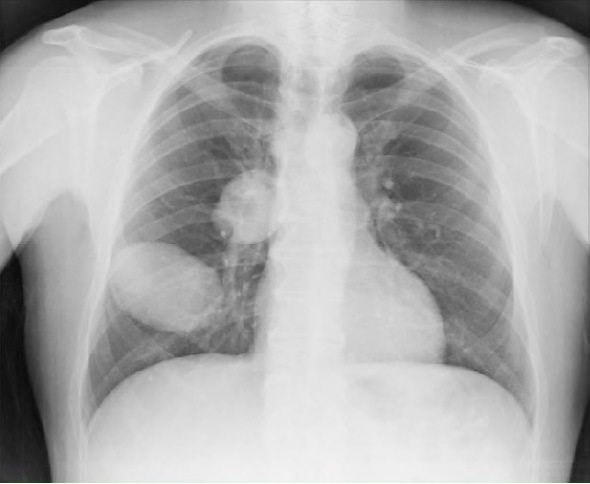

Se solicita una radiografía de tórax preferente desde Atención Primaria con fecha 14/04/15. El paciente acude a recoger el resultado el 20 de abril (figura 1). A la vista de las múltiples lesiones redondeadas de gran tamaño se contacta vía telefónica con el servicio de Urgencias del Hospital General de Villarrobledo, que solicita TAC abdominopélvico con contraste intravenoso y analítica completa; ambos se realizan el día siguiente. Al mismo tiempo contactan con el Servicio de Neumología, que realiza una espirometría ese mismo día y cita para una fibrobroncoscopia en menos de una semana (el 27 de abril).

Resultado del TAC toracoabdominal con contraste intravenoso (figura 2): masas quísticas de 67 y 75 mm de diámetro uniloculares polilobuladas en lóbulo inferior derecho; como primera posibilidad diagnóstica hidatidosis pulmonar.